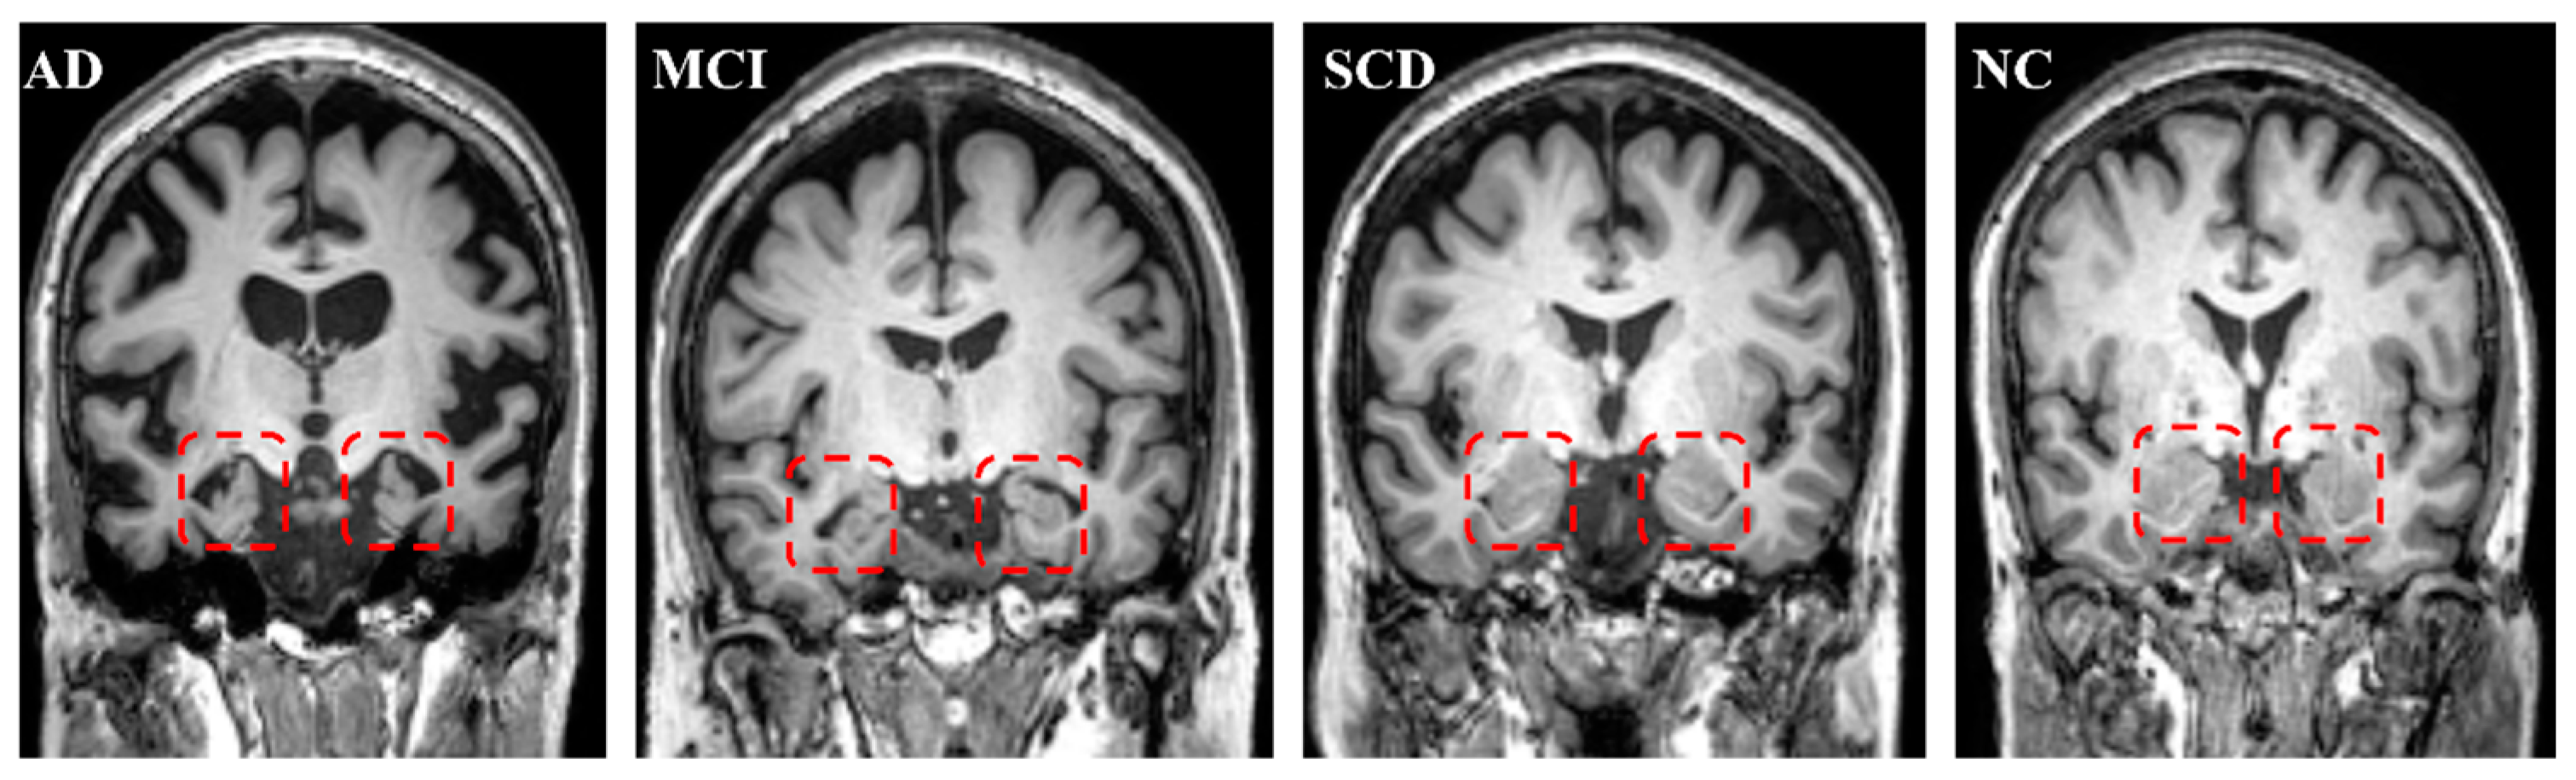

Figure 5.

Typical subjects for AD, MCI, SCD, and NCs. The red square contains the bilateral hippocampus. The atrophy of the bilateral hippocampus for AD is the most severe; MCI is intermediate. There was no hippocampal atrophy for SCD compared with NCs.